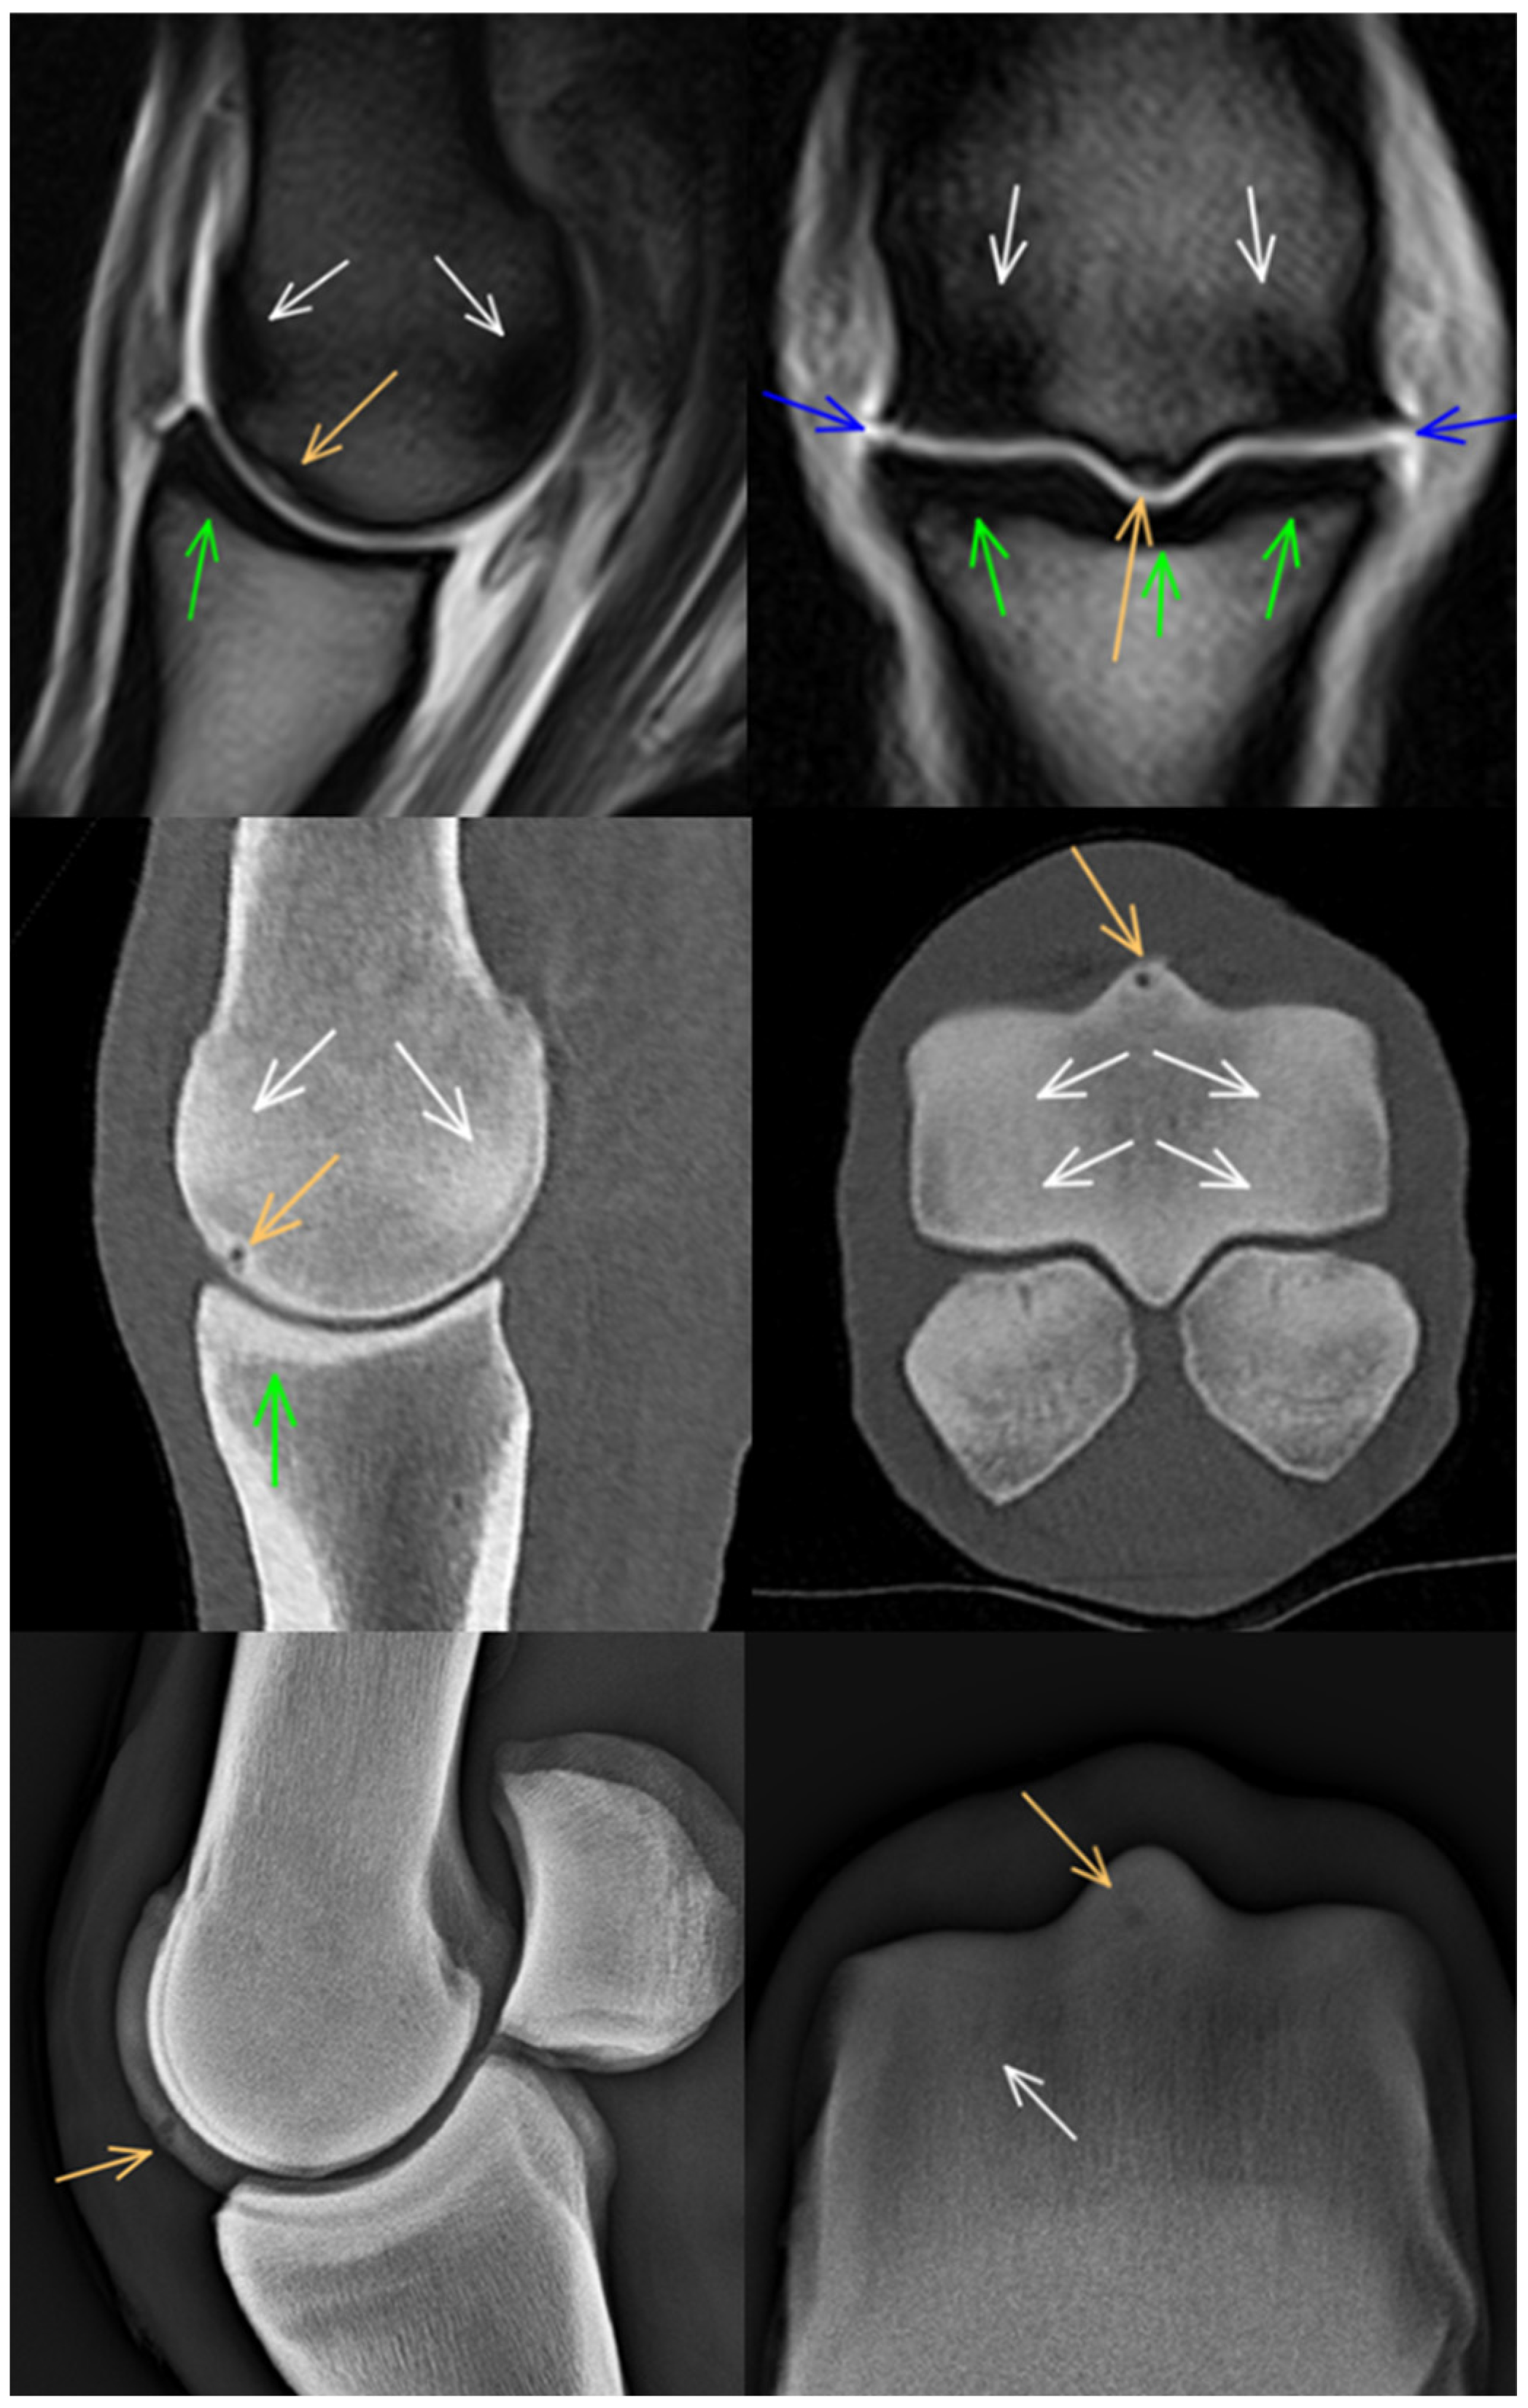

3.1. Third Metacarpal Bone

3.2. Proximal Phalanx

3.3. Proximal Sesamoid Bones

3.4. Soft Tissues